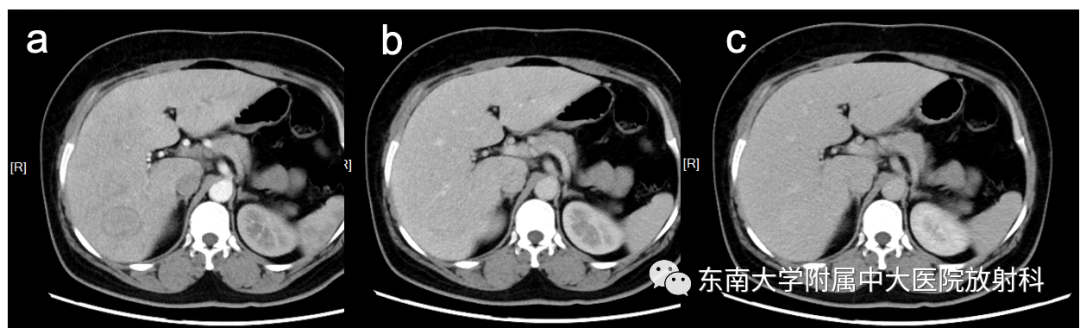

【PPT】肝细胞腺瘤

病史

女,47岁

主诉:右上腹不适2月

否认“高血压”、“糖尿病”、“肝炎”病史